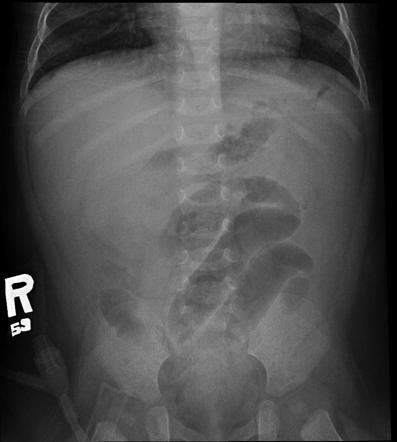

相关图片